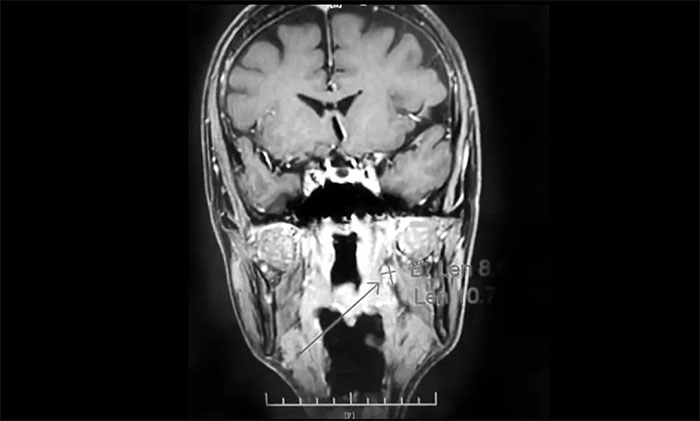

经MDT多学科会诊评估,制定以放疗为主的同步放化疗方案。治疗后复查MRI,患者左侧鼻咽部实性占位较前治疗明显减小;原左侧下颌腺区、咽旁肿大淋巴结已基本吸收好转,左颈部肿大淋巴结较前明显缩小。

▲ 放疗后复查MRI,肿瘤占位较前明显减小